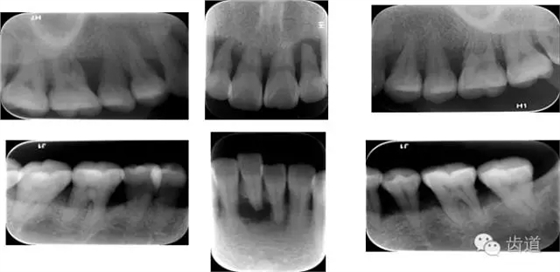

X線:根尖片、曲面斷層片(牙槽嵴頂,水平垂直吸收,程度)